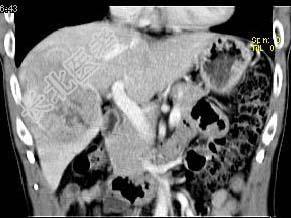

- 单项选择题根据所提供的图像,最可能的诊断是 ( )

A、肝血管瘤

B、FNH

C、肝癌

D、肝腺瘤

E、以上都不是